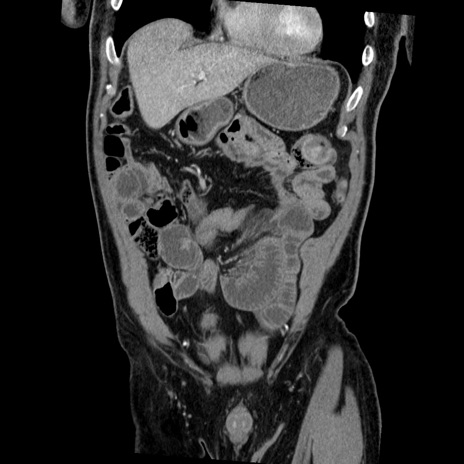

症例22(冠状断像)

【症例】50歳代男性

【主訴】腹痛

【現病歴】AVMからの被殻出血のため回復期リハ病棟入院中。 本日午後3時頃急に下腹部痛が出現した。

【既往歴】AVM、被殻出血、虫垂炎、高血圧

【身体所見】意識晴明、左半身不全麻痺、会話の理解は良好、36.5°C、腹部:膨隆、全体に板状硬、下腹部正中に圧痛点あり、反跳痛-、筋性防御不明、右下腹部にope scar

【データ】WBC 9400、CRP 0.06